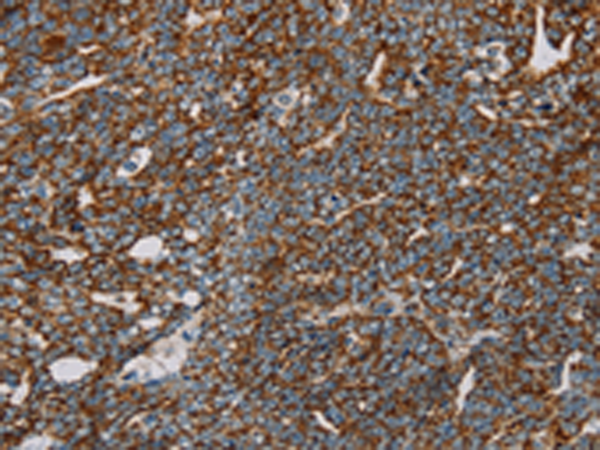

分类: 科研抗体货号: P01531别名: MORG1应用: WB,IHC反应种属: Human, Mouse, Rat

分类: 科研抗体货号: P01583别名: CI-30应用: WB,IHC反应种属: Human, Mouse

分类: 科研抗体货号: P01580别名: B8; CD14; CIB8; MC1DN13应用: WB,IHC反应种属: Human, Mouse

分类: 科研抗体货号: P01606别名: NS; E2IG3; NNP47; C77032应用: WB,IHC反应种属: Human

分类: 科研抗体货号: P01655别名: MPPB; P-52; MPP11; MPPP52; Beta-MPP应用: WB,IHC反应种属: Human, Mouse, Rat

分类: 科研抗体货号: P01604别名: CN1; CNI; CN-I; CN1A; CN-IA应用: IHC反应种属: Human, Mouse